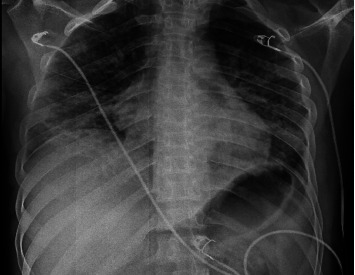

Introduction: People living with HIV (PLWH) are highly susceptible to respiratory infections, particularly pneumonia, which is often polymicrobial. A rapid decline in CD4 T lymphocytes, especially with concurrent influenza, increases the risk of Pneumocystis jirovecii pneumonia (PCP). Case Presentation: This report discusses a newly diagnosed Acquired Immunodeficiency Syndrome (AIDS) patient with influenza and PCP coinfection, highlighting diagnosis, follow-up, and prognosis. Conclusions: Community-acquired pneumonia is common in PLWH, especially among those not receiving antiretroviral therapies (ART). Co-infections with bacterial, viral, and fungal pathogens are common. Early identification of etiological agents and prompt treatment are crucial for improving patient outcomes.

Abstract Image